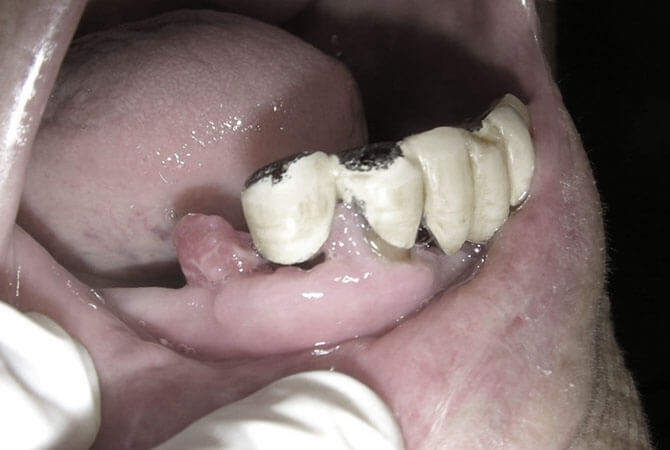

舌癌